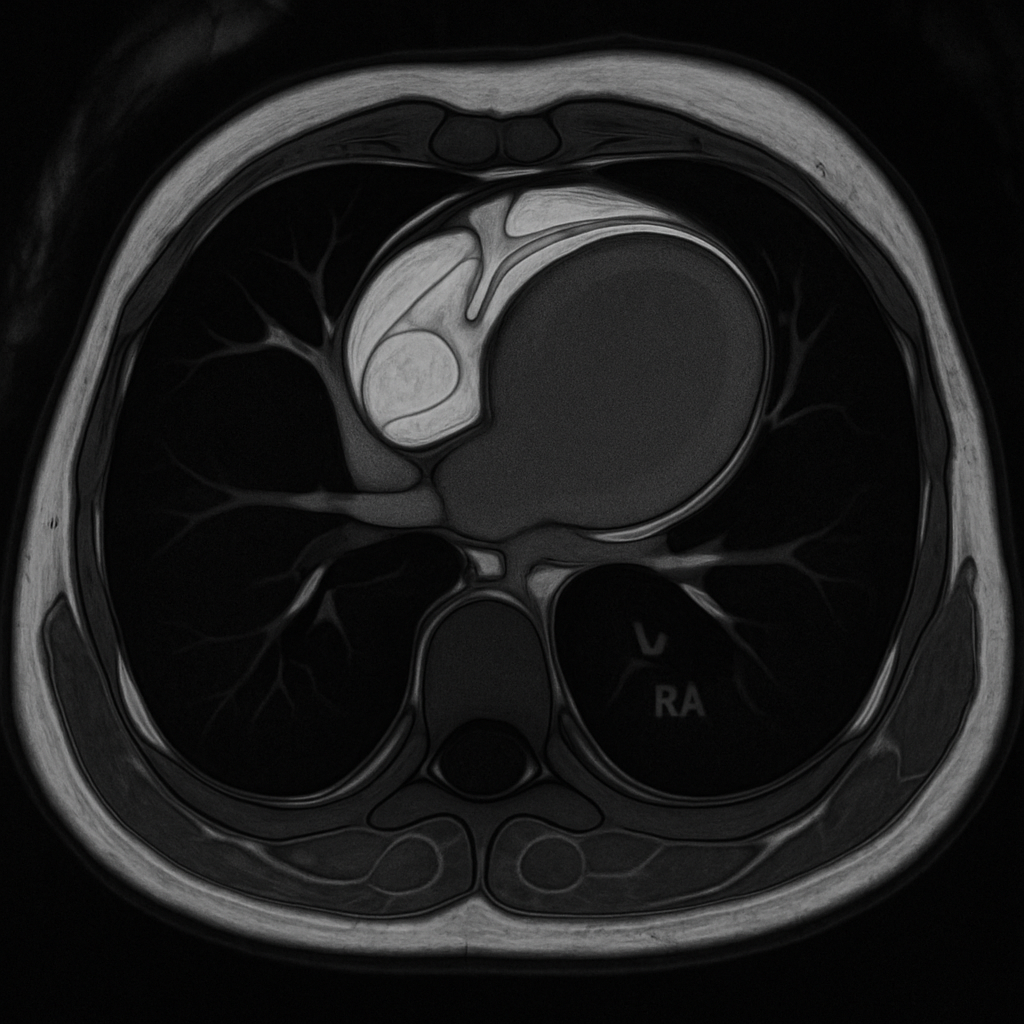

MRI — Short Axis Cine (Diastole)

Cardiac MRI short-axis (SA) view at mid-ventricular level during end-diastole. Balanced SSFP sequence showing bright blood in LV and RV cavities, dark myocardium, papillary muscles.

MRI AI Generated 2026-03-16

Ssfp Short Axis

bSSFP cine, mid-ventricular short axis, end-diastolic frame. Bright blood pool, dark myocardium.

OpenAI gpt-image-1